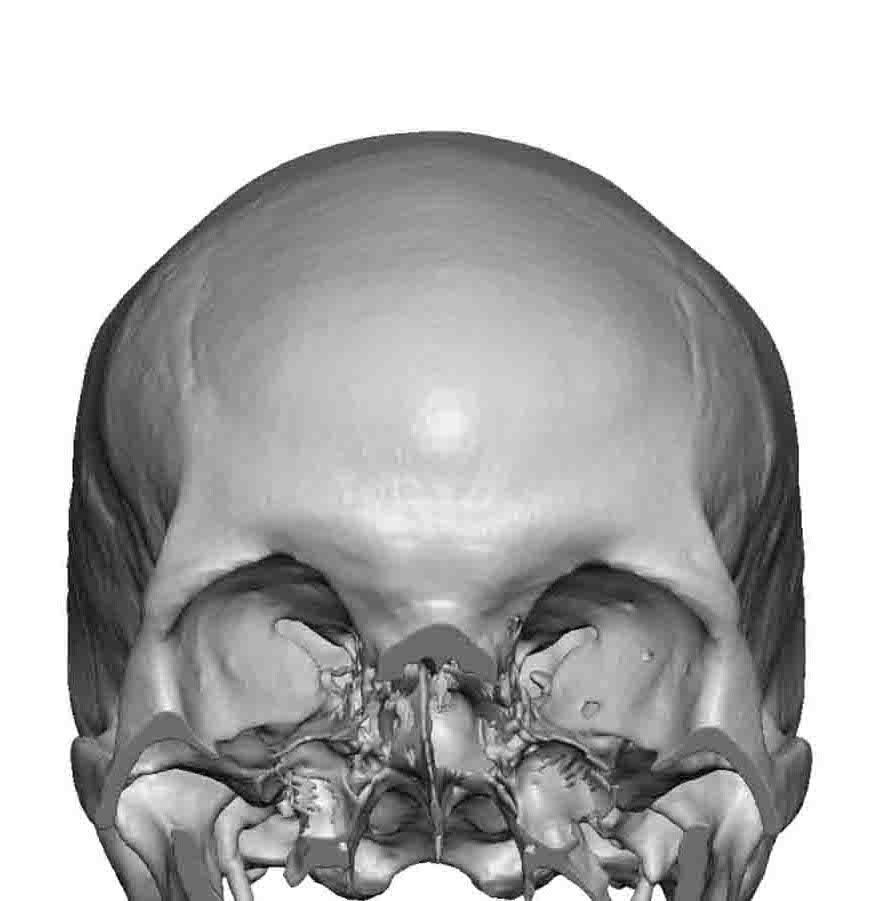

Desire for a higher and more prominent crown of the skull.

Crown of skull augmentation using a custom skull implant.

Desire for a higher and more prominent crown of the skull.

Crown of skull augmentation using a custom skull implant.